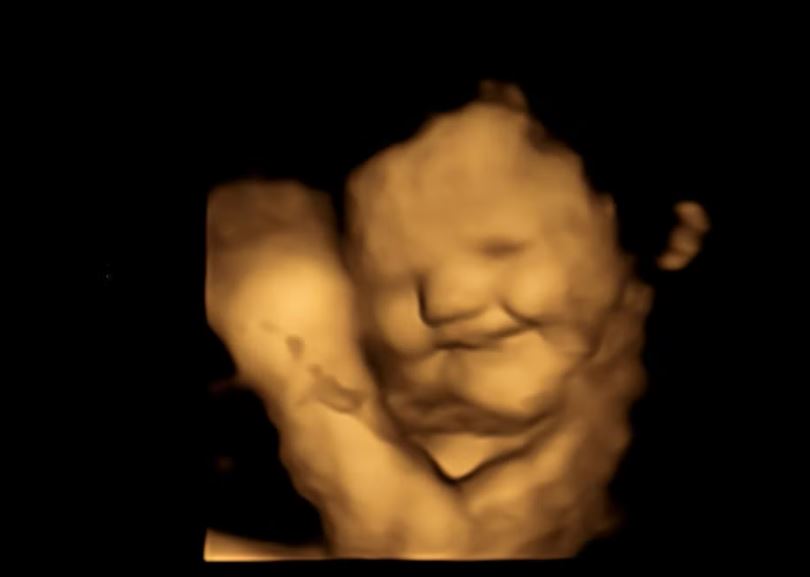

سائنس دانوں کی نئی تحقیق میں پتہ چلا ہے کہ رحم میں موجود بچے اپنی ماؤں کے کھانے پینے پر ردعمل دیتے ہیں، ماؤں کی جانب سے سبز سبزیاں چکھنے اور سونگھنے پر وہ منہ بنا لیتے ہیں اور گاجر کھانے پر وہ مسکراتے بھی ہیں۔

ڈرہم یونیورسٹی کے سائنس دانوں نے اس تحقیق کے دوران 100 حاملہ خواتین کے فور ڈی الٹراساؤنڈ سکین کیے تاکہ یہ معلوم کیا جا سکے کہ ان کی ماؤں کی جانب سے کھائے جانے والے کھانوں کے ذائقوں پر پیٹ میں موجود بچے کیسا ردعمل دیتے ہیں۔

ماؤں کی جانب سے گاجر کھانے کے بعد سب سے زیادہ  بچوں نے ’مسکرا کر‘ اپنا ردعمل ظاہر کیا جب کہ سبز گوبھی کھانے پر انہوں نے ’رونے والے چہرے‘ بنا کر اپنا ردعمل ظاہر کیا۔

تحقیق کے ایک حصے میں ماؤں کی 32 اور 36 ہفتوں کے حمل کے دوران سکیننگ کی گئی تاکہ پیٹ میں موجود بچوں کے چہروں کے سبز گوبھی اور گاجر کے ذائقوں پر رد عمل کو دیکھا جا سکے۔

انہیں ہر سکین سے 20 منٹ پہلے تقریباً 400 ملی گرام گاجر یا 400 سبز گوبھی کے پاؤڈر پر مشتمل ایک کیپسول دیا گیا اور انہوں نے سکیننگ سے ایک گھنٹہ پہلے تک کچھ بھی کھانے سے گریز کیا۔

دونوں گروپوں میں بچوں کے چہرے کے رد عمل سے ظاہر ہوتا ہے کہ گاجر یا سبز گوبھی کے ذائقے کی تھوڑی سی مقدار بھی ان کے ردعمل کو متحرک کرنے کے لیے کافی تھی۔